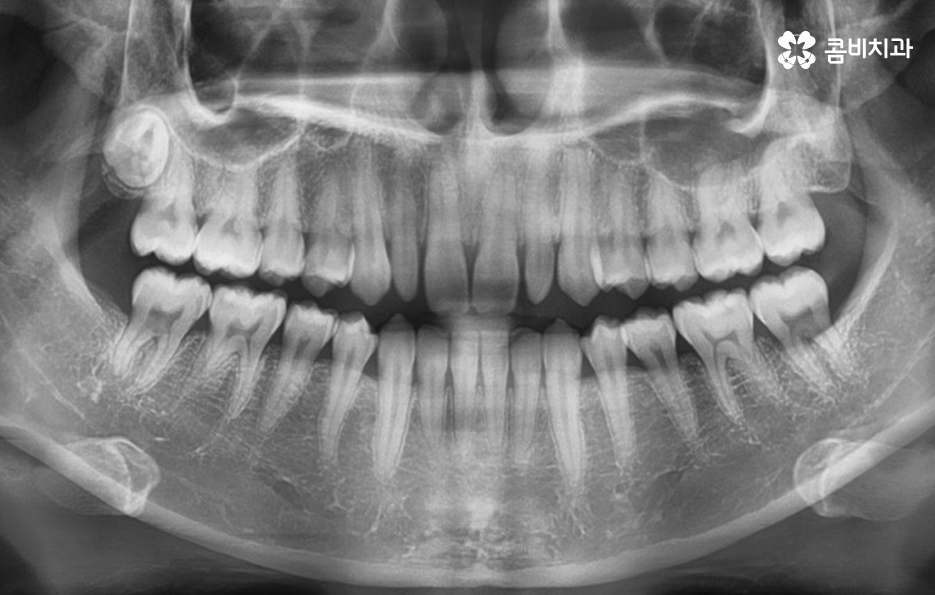

가지런한 치열을 위해서는 보통 치아교정에 대해서 생각하게 되지만

치아가 깨졌거나 심한 변색, 충치 그리고 왜소치와 같은 경우에는

라미네이트나 올세라믹과 같은 치료가 필요한데 위 케이스의 경우

전체적인 치아의 각도와 교합을 바로 잡고 왜소치와 앞니 깨짐을

올세라믹을 통해서 치료를 한 케이스 입니다.

왜소치는 이렇게 정상적인 치아에 비해 유독 작기 때문에

치아의 삭제를 하지 않고도 라미네이트 치료가 가능하며,

올세라믹은 치아를 약간 갈아내고 보철물을 씌워서

심미 치료가 가능합니다.

올세라믹은 세라믹 보철물로 치아 전체를 덮어 씌우는 방식으로

치아의 색과 모양은 물론 자연스러움을 위한 투명성까지도

갖추고 있으며 내구성도 높은 편이기 때문에 앞니가 깨졌거나

심한 변색, 충치, 왜소치 등의 치료에 많이 쓰입니다.